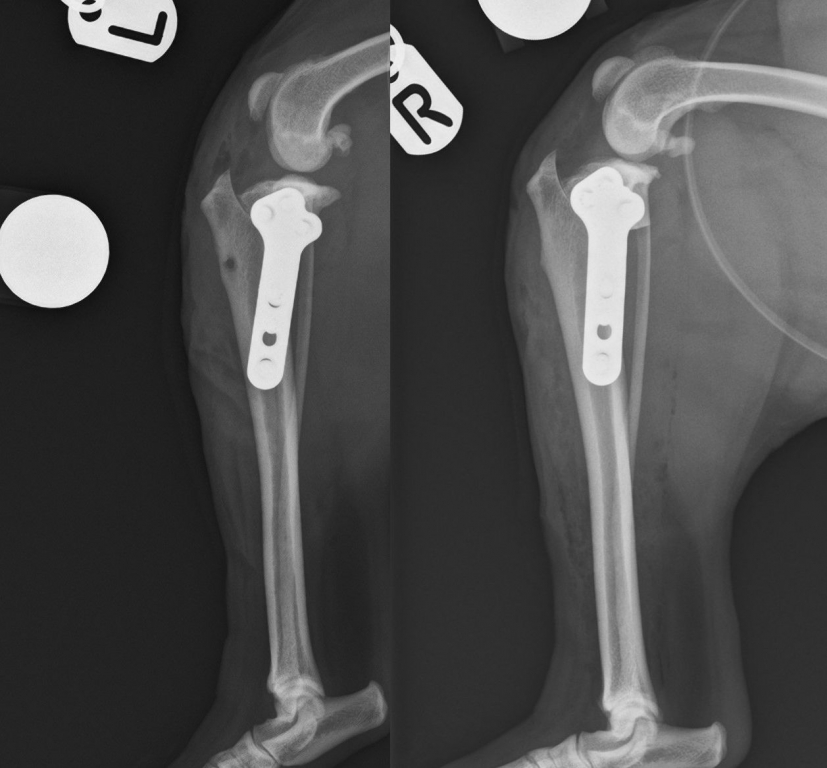

Jan performed a TPLO procedure on both stifle joints during one anaesthetic. Inspection of the stifle joints revealed a complete rupture of the cranial cruciate ligament bilaterally. In addition, a tear of the medial meniscus was identified in the left stifle and was removed via a caudal pole hemi-meniscectomy. The stifles were stabilised using a routine TPLO technique.